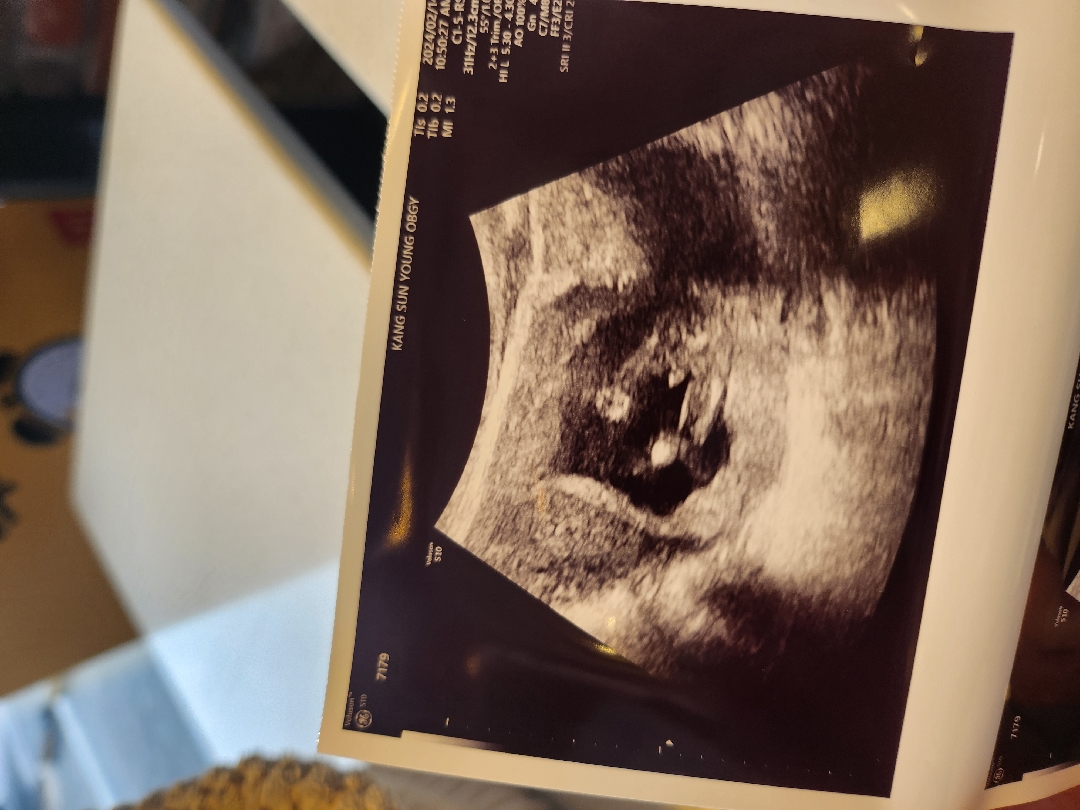

14주 초음파

빼도박도 못하는 아들맘인거죠?? ㅎㅎㅎ